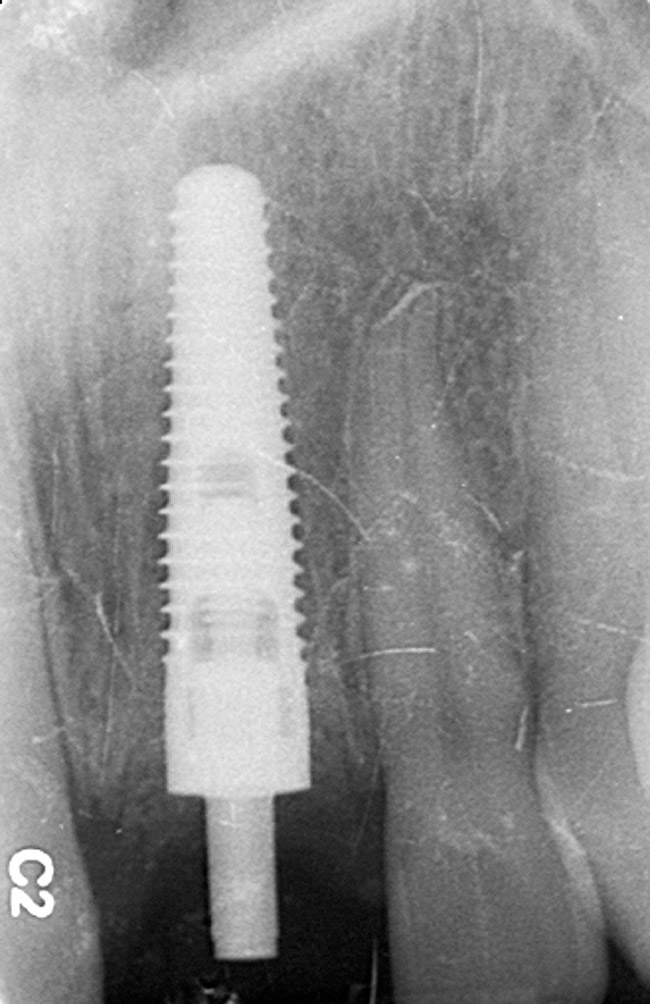

Figure 6  Confirmed ideal implant alignment with pontics in provisional bridge from Nos. 22 through 28—post-placement periapical view.

Figure 6

Six months later, the periodontist prepared osteotomies and placed three 3.25-mm x 13-mm implants using a vacuum-formed surgical guide fabricated by the restorative dentist (using a cast of the provisional bridge as a guide, as described by Block et al16); healing abutments were placed simultaneously. A post-implant radiograph confirmed good implant alignment with the pontics of the provisional from teeth Nos. 22 through 28 (Figure 6).